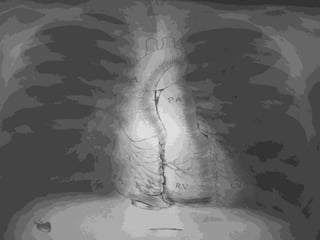

Before going to our topic lets have

a look at normal chest X ray PA

view and structures normally

visualize in it